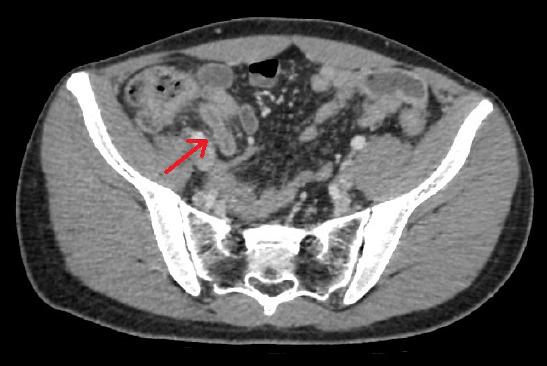

Acute appendicitis is one of the most common abdominal surgical emergencies worldwide. Clinical diagnosis is possible in most of the cases although imaging modalities may become necessary if the diagnosis is uncertain. Appendectomy, preferably the laparoscopic ap-proach, still remains the gold standard treatment to date. The pathophysiology usually includes luminal obstruction by an appendicolith or lymphoid hyperplasia and rarely parasitic infections. In this report, we present an extremely rare case of a patient with diagnosis of bipolar disorder and a history of trichophagia resulting in trichobezoar formation within the appendiceal lümen leading to acute appendicitis.

急性阑尾炎是全球最常见的腹部外科急症之一。虽然在诊断不确定的情况下可能需要影像学检查,但大多数情况下可以通过临床诊断来确定。阑尾切除术,最好是腹腔镜方法,仍然是迄今为止的金标准治疗方法。其病理生理学通常包括阑尾腔内的阑尾石或淋巴组织增生导致的管腔阻塞,很少发生寄生虫感染。在本报告中,我们介绍了一例极为罕见的病例,患者诊断为双相情感障碍,并有拔毛癖史,导致毛球在阑尾腔内形成,导致急性阑尾炎。